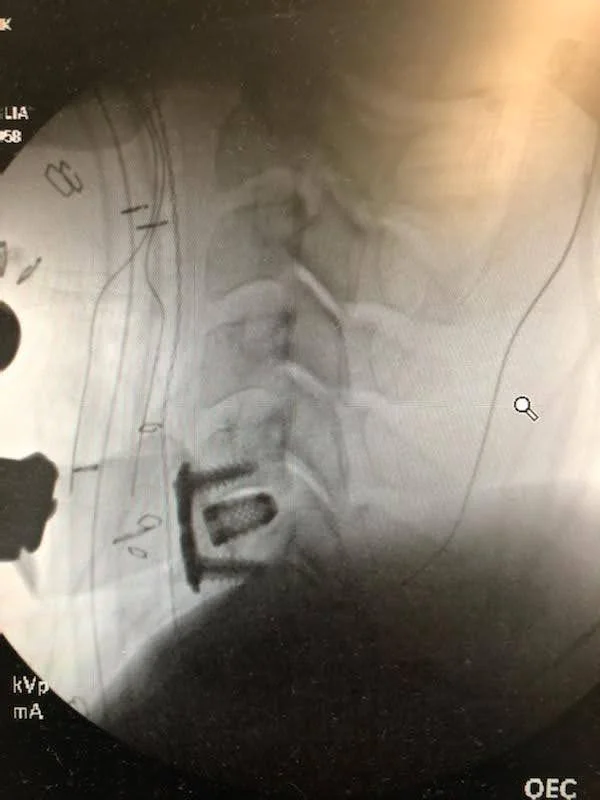

Next a cervial MRI was ordered.

There is a problem between C4 & C5.

They asked me to go via ambulance to the ER and I was to have emergency surgery they next day.

ACDF procedure

When I came to, my first thought was, wow I can feel my feet.

During the next couple hours, electrical like shocks of relief shot through my chest and my heart and lungs began to receive life.

My heart relaxed. My breathing got deeper.

Relief.

About 80% of my syptoms resided.